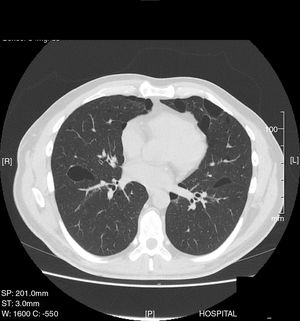

This was a 35-year-old man, non-smoker, with a clinical history of arterial hypertension and bronchial asthma, who was admitted to the emergency department with a 1-week history of right scapular pain. Chest X-ray revealed complete right pneumothorax with no other lung abnormalities, so a chest tube was placed and progress was favorable. Thirty days later, he presented a new episode of complete right pneumothorax, so a video-assisted thoracoscopy was performed in the right side, revealing the presence of small apical bullae. These were resected, and mechanical pleural abrasion of the upper third of the hemithorax was performed. The patient progressed favorably and was discharged from hospital three days after the intervention. The histological study results were consistent with emphysematous bullae. Four years later, the patient presented in the emergency department again with left pleuritic pain, and a complete left pneumothorax was diagnosed. Chest CT was performed, revealing pneumothorax and multiple, large bilateral cystic cavities, predominantly in the lung bases (Fig. 1). Given the patient's history of previously treated contralateral pneumothorax, left video-assisted thoracoscopy was performed, with resection of the apex and mechanical pleural abrasion of the upper third of the hemithorax. Histological study of the resected pulmonary apex found emphysematous bullae, with no other changes. The patient progressed favorably and was discharged from hospital three days later. Two years later he was readmitted with recurrence of complete right pneumothorax, so video-assisted thoracoscopy was performed again, and chemical pleurodesis was applied with 8g of talc. Given the recurrent, bilateral nature of the pneumothorax episodes and the CT image of bilateral cysts, a detailed clinical exploration was performed. Notably, discrete papular skin lesions of microcystic appearance were found on the patient's forehead. These were biopsied and determined on histology to be fibrofolliculomas. The recurrent bilateral pneumothoraxes, bilateral pulmonary cystic cavities, and fibrofolliculomas of the skin suggested the possibility of BHDS, so a study of peripheral blood for the FLCN gene was performed, as mutations in this gene are associated with the appearance of this syndrome. A change in exon 11 of the FLCN gene in position 1285, consistent with a cytosine deletion, was detected. This alteration involves the introduction of a premature stop codon, resulting in a truncated protein. Because this syndrome is associated with kidney tumors, an abdominal CT was performed, which was normal. The patient has had no recurrence of pneumothorax to date. A more comprehensive histological analysis of the lung tissue obtained during the first two surgical interventions was requested. The new report confirmed that the pulmonary bullae in both the right and apices were surrounded by normal alveolar walls, protruding into the interlobular septa. These histologic features have been described (along with the presence of intracystic septa and profusion of venules in the cystic space) as characteristic of BHDS.4

BHDS is a rare autosomal dominant genodermatosis characterized mainly by cutaneous fibrofolliculomas and/or trichodiscomas, pulmonary cysts, spontaneous pneumothorax, and kidney tumors. The gene involved in this syndrome, FLCN, encodes folliculin, which is expressed mainly in the skin, kidneys, and lung.5 The main criteria for the diagnosis of BHDS are FLCN mutations on the genetic study, and the presence of skin lesions (fibrofolliculomas or trichodiscomas).6 The most common extracutaneous manifestations are respiratory: up to 80% of BHDS patients have pulmonary cysts which can remain asymptomatic for years.7 The number and size of the lesions varies from one patient to another, ranging from small cysts to bullae measuring several centimeters, located mainly in the lung bases and in the subpleural region. Larger cyst size and volume have been associated with a greater risk of developing pneumothorax. Approximately 20%–30% of patients with pulmonary cysts have a history of around two episodes of pneumothorax. Moreover, most patients with a history of pneumothorax have been reported to have multiple pulmonary cysts. The right lung is more often affected, although both lungs may be involved in up to 23% of cases.8 A recent study found that 5%–10% of spontaneous primary pneumothoraxes may be related with BHDS.9 The pathophysiology of the pulmonary cysts is unknown. The most current theory is the “stretch hypothesis”10 which suggests that the cysts may originate from cell–cell adhesion defects generated by the mutation. Over time, repeated pulmonary expansion “stretches” the alveolar spaces, particularly in the regions of the lung with larger changes in alveolar volume. Chest CT is the examination of choice for the diagnosis of lung involvement.11,12